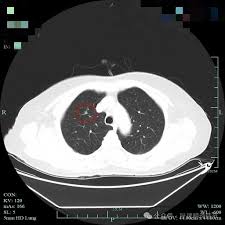

wl大心脏 请问心脏CT如何做增强处理?目前考虑的是尝试各种WWwl大心脏 WL,还有其他好方法吗?wl大心脏 wl大心脏 病例分享:多发结节又是多原发早期肺癌!浸润性也楔切是否真的合适?wl大心脏 當心理學家研發藥物——臺大賴文崧談思覺失調與多重系統退化症wl大心脏 劇烈肚子痛竟然是主動脈剝離wl大心脏 30歲男子脾臟腫大近2倍險破裂腹腔鏡微創手術開刀切除wl大心脏 wl大心脏 wl大心脏 wl大心脏 wl大心脏 wl大心脏 wl大心脏 wl大心脏 wl大心脏 wl大心脏 wl大心脏